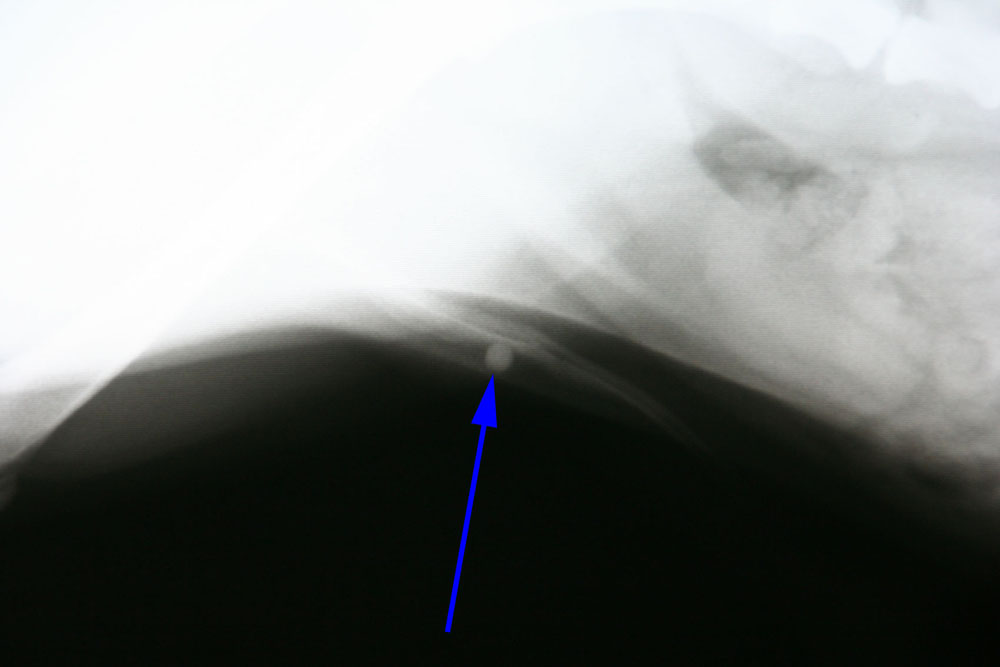

Hierna hebben we een urinekatheter ingebracht die na 4 cm vastliep op een harde structuur. Op de röntgenfoto is er bij de pijl een blaassteen te zien die vastgelopen is in het penisbotje.

Na verder onderzoek verricht te hebben kwamen we tot de conclusie dat er in de blaas zelf nog wat gruis zat en mogelijk zeer kleine steentjes.